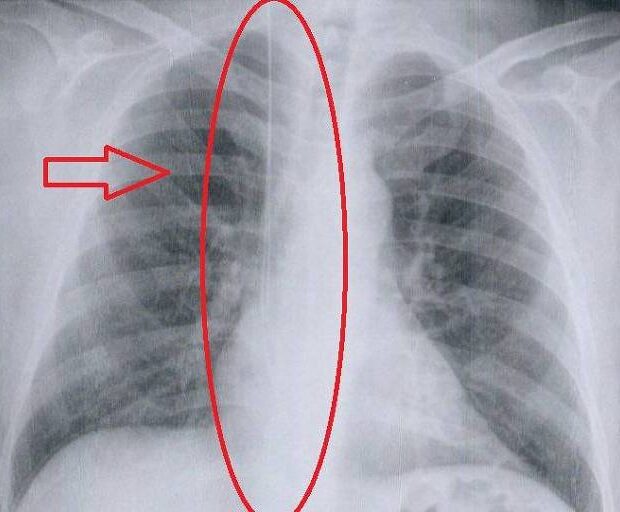

Morador de Itanhaém, no litoral paulista, Vanes de Jesus da Silva, 47, ficou com um fio-guia esquecido entre a veia jugular, no pescoço, e o átrio direito do coração após um procedimento de preparação para hemodiálise. A cirurgia foi realizada em julho de 2022, numa clínica prestadora de serviço ao SUS (Sistema Único de Saúde) na cidade de São Vicente.

“Mesmo após a retirada do cateter, meu pai reclamava de muita dor, então marcamos um raio-x e descobrimos que haviam esquecido um fio-guia dentro dele”, diz Jullyana Dionísio, 24, filha de Vanes.

No hospital da capital paulista, entretanto, o item foi parcialmente removido. “Nos disseram que a parte próxima ao pescoço formou uma fibrose, então meu pai continua vivendo com um pedaço de fio de 10 centímetros”, informa Jullyana.